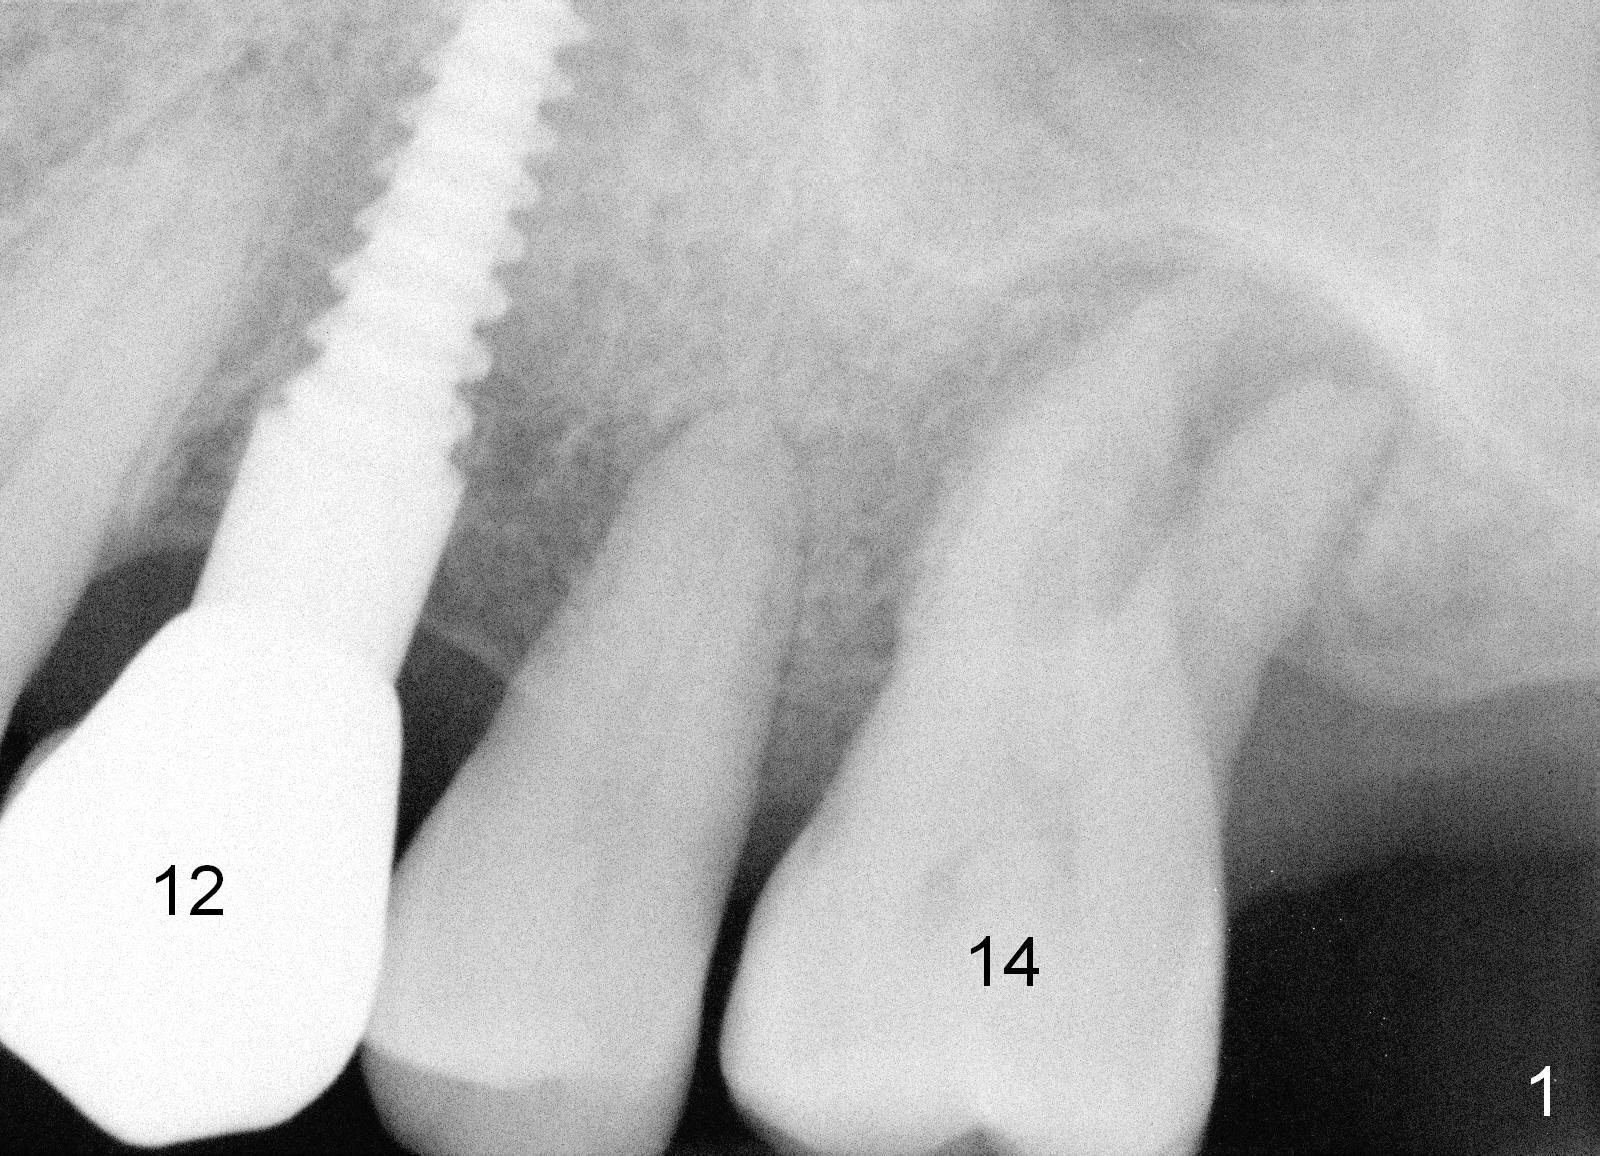

A 52-year-old man (DM) will return for #14 extraction and immediate implant nearly 2 years after #12 crown cementation. There is more bone loss distally than mesially. Clinically, the palatal recession is excessive (Fig.3). After socket debridement and 2% Xylocaine/1:50,000 Epinephrine gauze packing, osteotomy will be initiated in the buccomesial aspect of the septum, if the latter is present. Use 4.5 or 5x17 mm tap to test stability and more importantly determine how much thread exposure can occur palatally before placing a 14 or 17 mm long implant (Fig.2). A fair amount of bone graft will be inserted distopalatally (red circles in Fig.2). If primary stability is achieved, use an immediate provisional to close the socket opening.